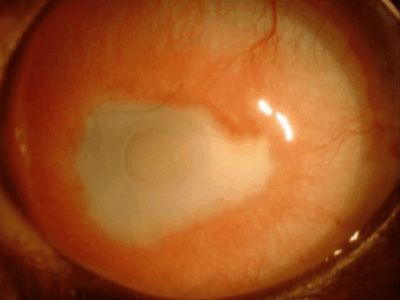

黒目が赤い場合

血管新生

・角膜炎

・角膜潰瘍

・猫ヘルペス角膜潰瘍

・パンヌス

角膜には本来血管がなく透明ですが、炎症、傷、刺激などが慢性化すると角膜周囲から血管が伸びてきます。だいたい1日あたり1mm伸びるといわれています。原因としては角膜炎、角膜潰瘍、乾性角結膜炎(ドライアイ)、パンヌスなどがあります。